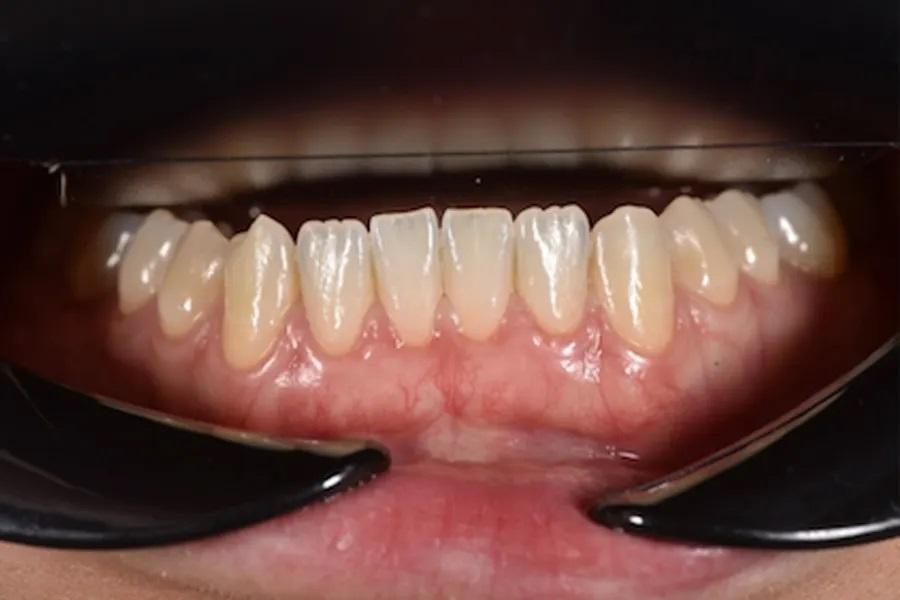

Пациентка 31 года обратилась с следующими внутриротовыми признаками: передний открытый прикус, скученность зубов на обеих челюстях, отрицательный торк коронок, начальные «черные треугольники» и тонкий пародонтальный фенотип/биотип с ранними рецессиями. Внеполостная картина включала десневую улыбку с высокой подвижностью верхней губы, асимметрию зубных дуг и задних щечных коридоров, а также несмыкание губ (фото 1 – 3). Совокупность этих факторов повышает эстетические и пародонтальные риски и обосновывает выбор интрузии боковых зубов вместо интрузии передних.

Фото 1. Исходная внутриротовая оценка в положении максимальной интеркуспидации. Отмечаются передний открытый прикус, скученность зубов с отрицательным торком коронок, начальные стадии «черных треугольников» (особенно между зубами 11 и 21), асимметричные «провисающие» задние щечные коридоры верхней челюсти и тонкий биотип, предрасполагающий к рецессиям, особенно у молодых пациентов.